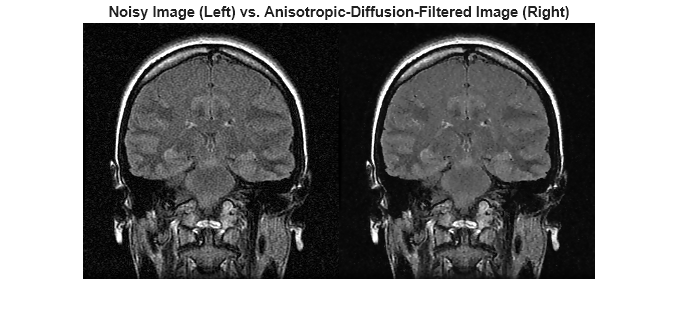

영상에 대한 비등방성 확산 필터링